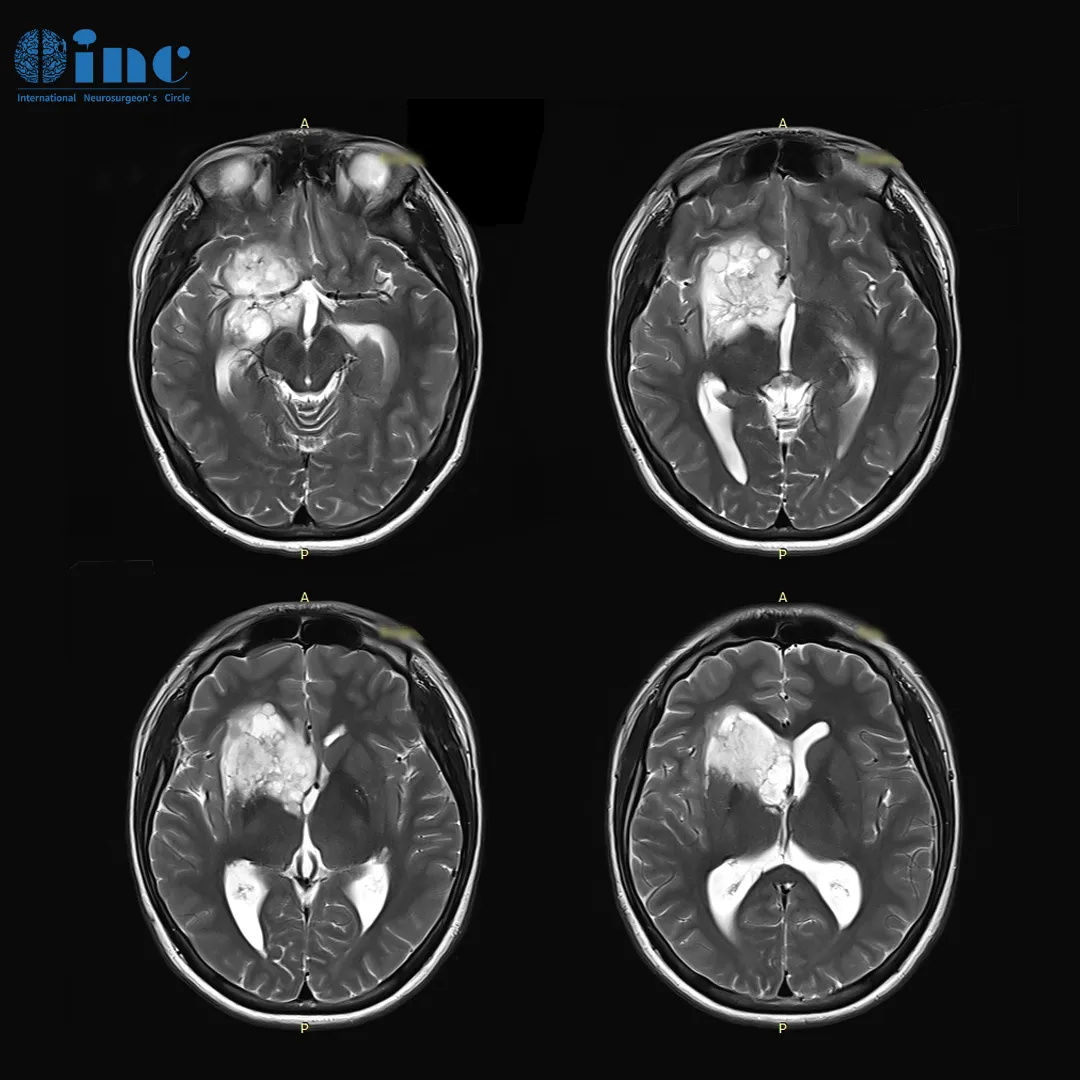

小磊术前MRI影像显示右额、颞、基底节区、侧脑室前角区占位

16岁小磊(化名)在一次全身体检中查出“颅内占位性病变”,然后去国内三甲医院确诊。小磊的胶质瘤主要位于基底节部位,属于大脑功能区,目前手术风险较大,较大占位压迫岛叶、和血管神经关系密切,切除肿瘤时较易造成脑组织神经血管损伤,90%以上会术后出现神经损伤如瘫痪、记忆障碍等,在这个位置手术不容有失,否则面临的可能是终身的瘫痪,生活不能自理。

手术情况:巴教授通过右侧额颞开颅暴露病灶并在保护神经功能情况下较大水平切除肿瘤,随后借助术中MRI对照进行了显微外科肿瘤切除术,手术过程中未出现并发症。手术做完当天,小磊成功拔管并转入ICU。术后2天,意识清醒,无新发神经系统损伤。转回神经外科普通病房,并在康复治疗师的指导下开始活动。小磊很快就开始独自行走。

术前术后MR磁共振对比,术前右额、颞、基底节区、侧脑室前角区较大占位,压迫岛叶及脑室,脑室增大。术后MR提示肿瘤近全切,占位效应解除,无新发脑损伤等。